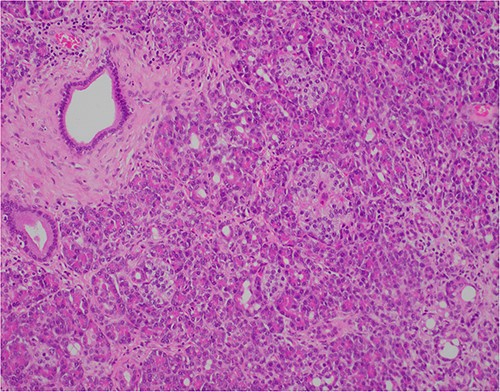

At outpatient phone clinic review 2 months post-surgery, the patient had recovered well, and his pre-operative symptoms of nausea, vomiting and pain had completely resolved. The histopathology of the gallbladder found chronic cholecystitis with cholelithiasis, in addition to a 6 mm focus of pancreatic heterotopia in the gallbladder wall. This heterotopic tissue contained acini, ducts and islet cells, classifying it as Type I pancreatic heterotopia (Figs 1–3).

×2 objective lens; low-magnification photograph showing an area of pancreatic heterotopia.